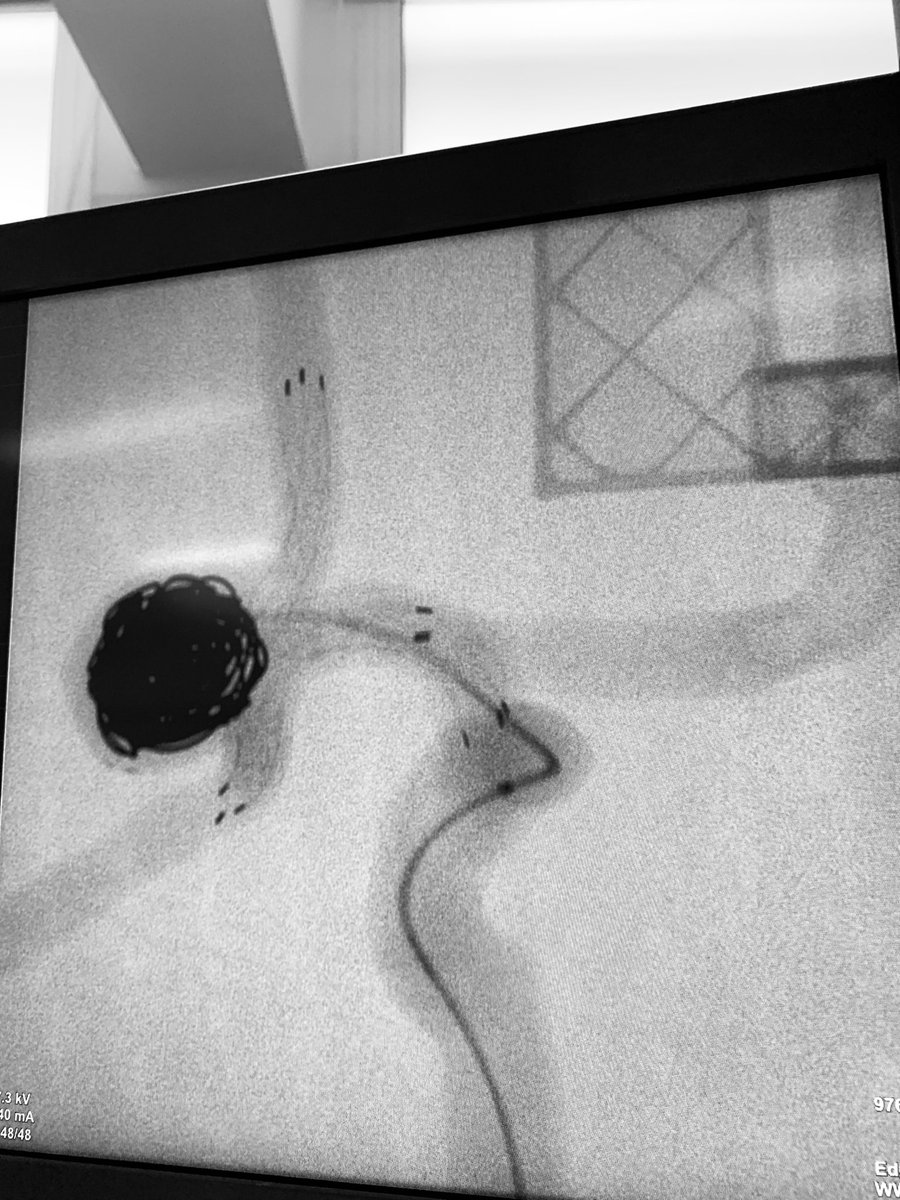

NUEVO UNBOXING. La Sra. Raquel González, especialista de producto para Medtronic España, nos presenta el unboxing para embolización de aneurismas con coils y acceso radial de Medtronic.

youtu.be/_I_4tdNYVQc

#unboxing #coiling #radialfirst